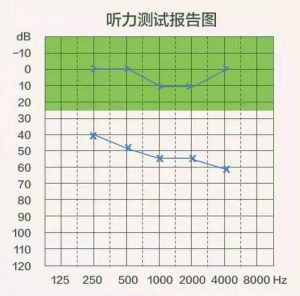

骨导阈值正常或接近正常,气导阈值升高,气骨导差大于10DB,低频损失较重,呈平坦型或上升曲线型,不舒适阈值较高,早期患者的言语可懂度无明显下降,主要临床表现为听不到,因为传音障碍衰减了声音。